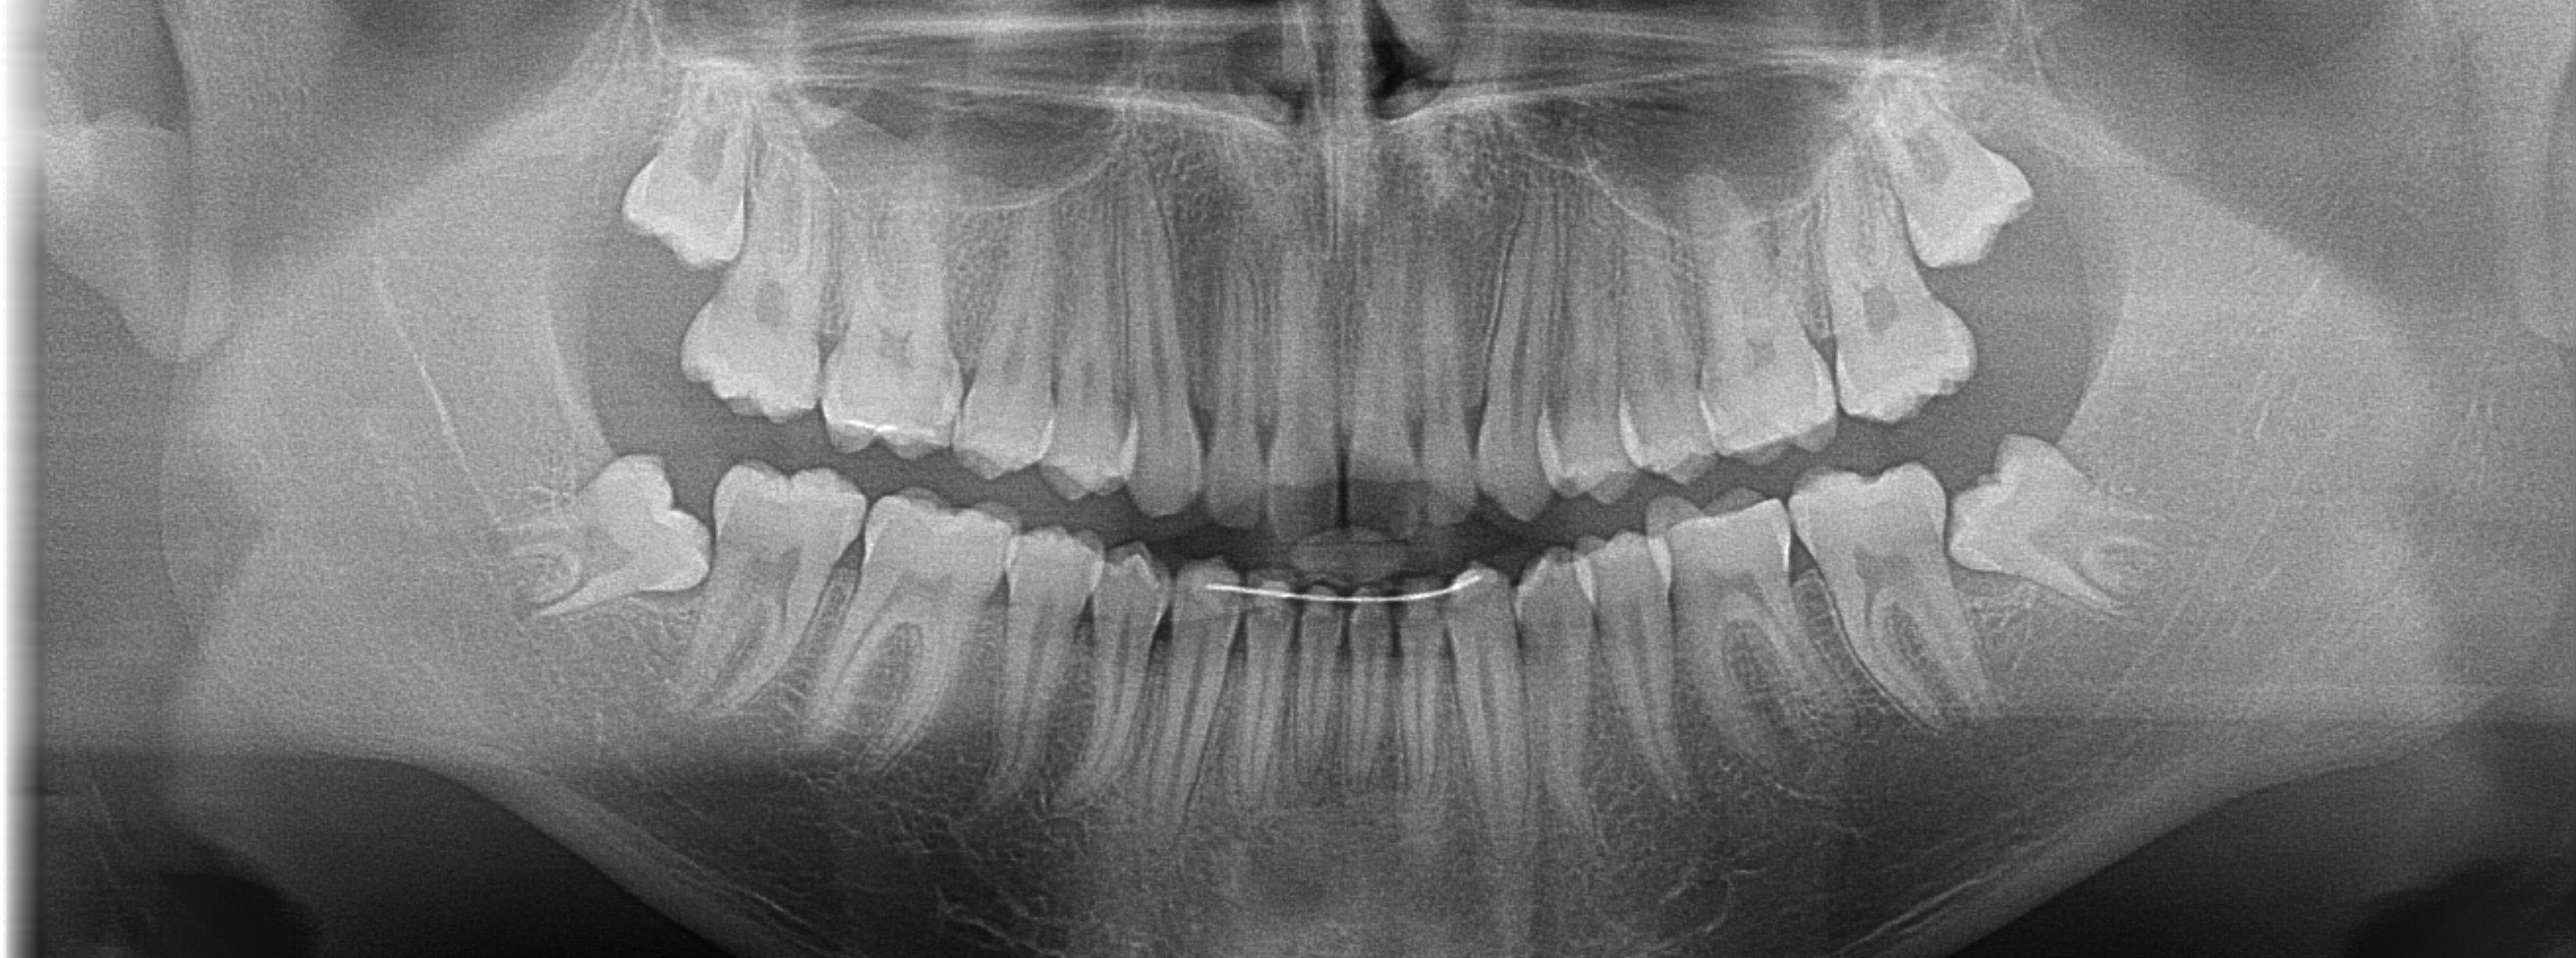

Pani Kasia z Tychów zgłosiła się z powodu resorpcji przy wcześniej leczonym kanałowo zębie. Resorpcja to nieodwracalny proces polegający na niszczeniu korzenia zęba w procesie autoimmunologicznym. Aby wyeliminowywać stan zapalny jedyną metodą jest usunięcie chorobowo zmienionego zęba. Ze względu na dolegliwości bólowe niezwłocznie przystąpiono do wykonania zabiegu usunięcia zęba, jednocześnie zabezpieczając kość pod planowany w przyszłości implant. Ubytek po usuniętych korzeniach zęba zregenerowano biomateriałem oraz odwirowanym osoczem własnym Pacjentki (PRF).

Po uformowaniu kości w miejscu usuniętych korzeni, posadowiono implant.

Pacjentka oczekuje na wykonanie korony.